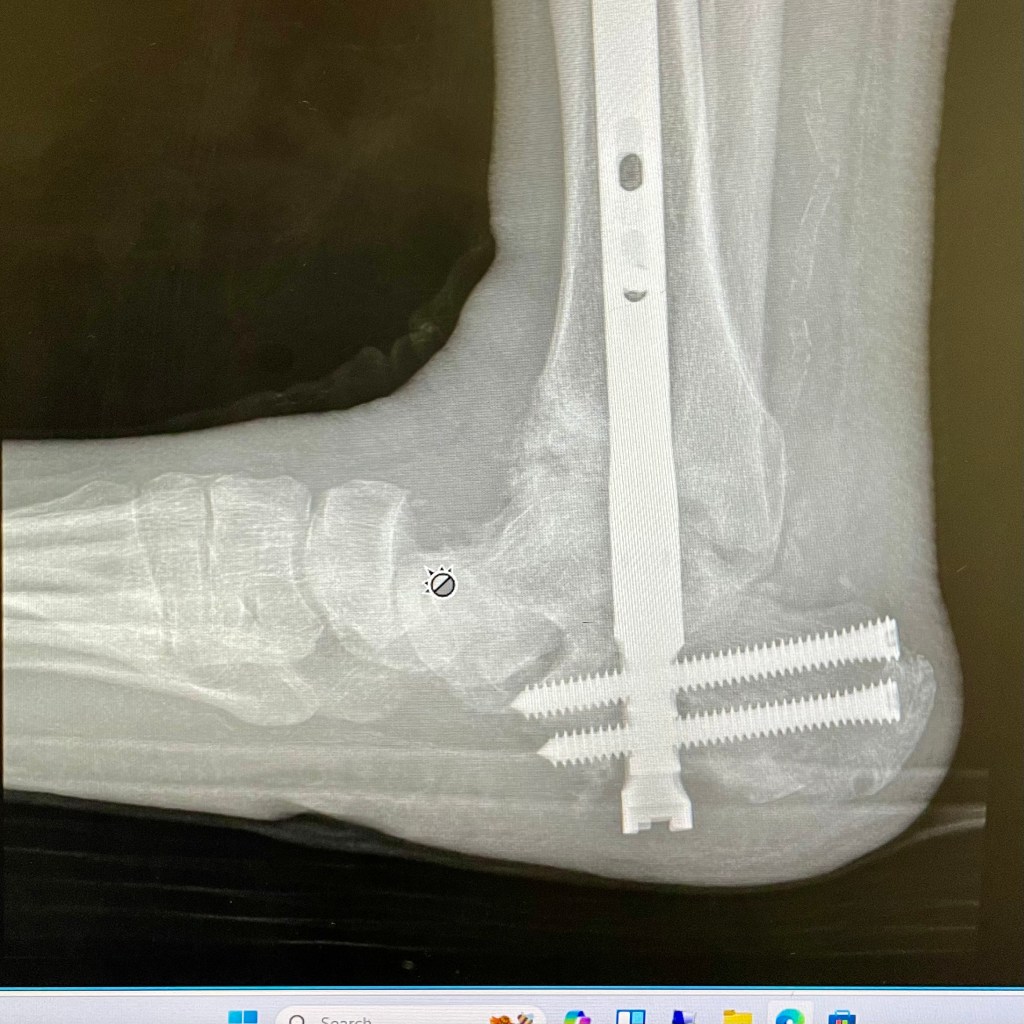

Here are some x-rays of my foot:

From top left to bottom, the dates are:

• February 7, 2024

• April 22, 2024

• May 13, 2024

• Today, May 20, 2024

You can see clearly that my ankle is dislocating downwards in the front. There is a growing hole right before you get to the toe bones. The problem was apparent on the May 13th x-ray, but much more obvious today. The other ankle surgeon at the office, a church friend, said that the bone is softer/weaker due to Charcot Foot, and usually that causes dislocations, fractures, and bone disintegration. By giving me another non-weight bearing cast, they hope to stabilize the ankle, and have it try to heal on its own.

Based on my luck so far, that is not likely. I will probably need more surgeries, including external fixators on the foot/ankle again. In the meantime, we are still waiting for another CT scan to get more clarity on what is happening.